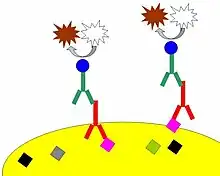

For immunohistochemical detection strategies, antibodies are classified as primary or secondary reagents. Primary antibodies are raised against an antigen of interest and are typically unconjugated (unlabeled), while secondary antibodies are raised against immunoglobulins of the primary antibody species. The secondary antibody is usually conjugated to a linker molecule, such as biotin, that then recruits reporter molecules, or the secondary antibody itself is directly bound to the reporter molecule.[3]

The direct method is a one-step staining method and involves a labeled antibody (e.g. FITC-conjugated antiserum) reacting directly with the antigen in tissue sections. While this technique utilizes only one antibody and therefore is simple and rapid, the sensitivity is lower due to little signal amplification, in contrast to indirect approaches.[3] However, this strategy is used less frequently than its multi-phase counterpart.

The indirect method involves an unlabeled primary antibody (first layer) that binds to the target antigen in the tissue and a labeled secondary antibody (second layer) that reacts with the primary antibody. As mentioned above, the secondary antibody must be raised against the IgG of the animal species in which the primary antibody has been raised. This method is more sensitive than direct detection strategies because of signal amplification due to the binding of several secondary antibodies to each primary antibody if the secondary antibody is conjugated to the fluorescent or enzyme reporter.[3]

Further amplification can be achieved if the secondary antibody is conjugated to several biotin molecules, which can recruit complexes of avidin-, streptavidin- or NeutrAvidin protein-bound enzyme.[3] The difference between these three biotin-binding proteins is their individual binding affinity to endogenous tissue targets leading to nonspecific binding and high background; the ranking of these proteins based on their nonspecific binding affinities, from highest to lowest, is: 1) avidin, 2) streptavidin and 3) NeutrAvidin protein.

Monoclonal antibodies

Many proteins shown to be highly upregulated in pathological states by immunohistochemistry are potential targets for therapies utilising monoclonal antibodies. Monoclonal antibodies, due to their size, are utilized against cell surface targets. Among the overexpressed targets are members of the EGFR family, transmembrane proteins with an extracellular receptor domain regulating an intracellular tyrosine kinase.[17] Of these, HER2/neu (also known as Erb-B2) was the first to be developed. The molecule is highly expressed in a variety of cancer cell types, most notably breast cancer. As such, antibodies against HER2/neu have been FDA approved for clinical treatment of cancer under the drug name Herceptin. There are commercially available immunohistochemical tests, Dako HercepTest, Leica Biosystems Oracle[18] and Ventana Pathway.[19]